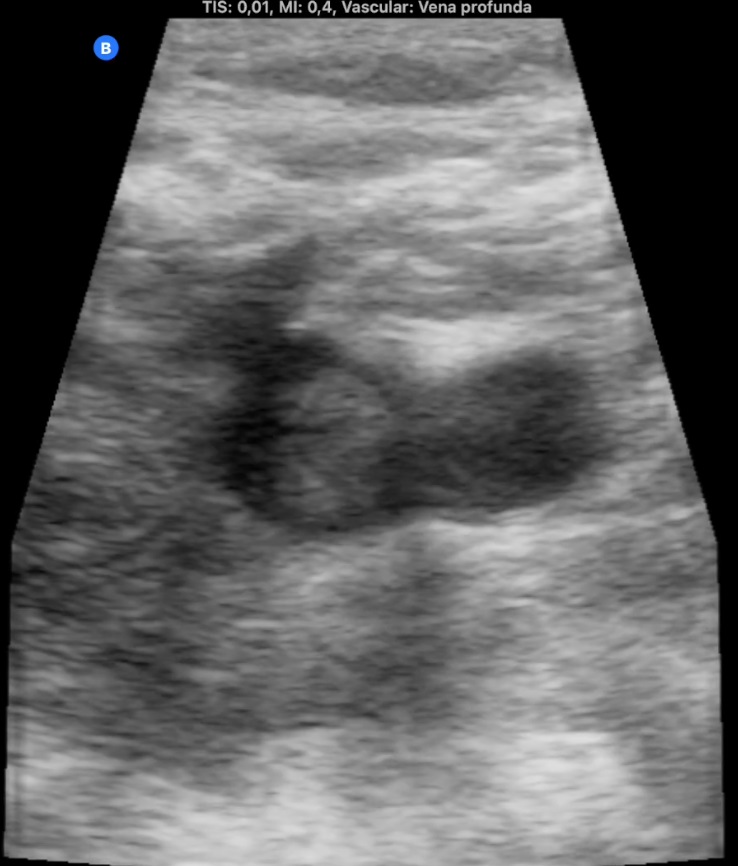

La ecografía pulmonar muestra microconsolidación y líneas B en campo posteroinferior derecho (imagen 1). Ante el antecedente de inmovilización y TEP previo, preguntamos por edemas y refiere inflamación en miembro inferior izquierdo, constatándose cierto aumento de perímetro. La ecografía de MII muestra trombo hiperecogénico femoropoplíteo con captación de Doppler periférico (imagen 2, 3 y 4).

TEP y TVP secundarios a inmovilización.

El angioTAC confirma TEP de arteria pulmonar principal derecha. Ingreso en Neumología para vigilancia. Estudio de trombofilia negativo. Anticoagulación indefinida por dos episodios de TVP/TEP.